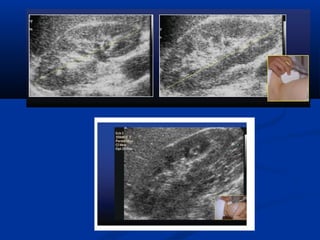

Hình aûnh bình thöôøngHình aûnh bình thöôøng